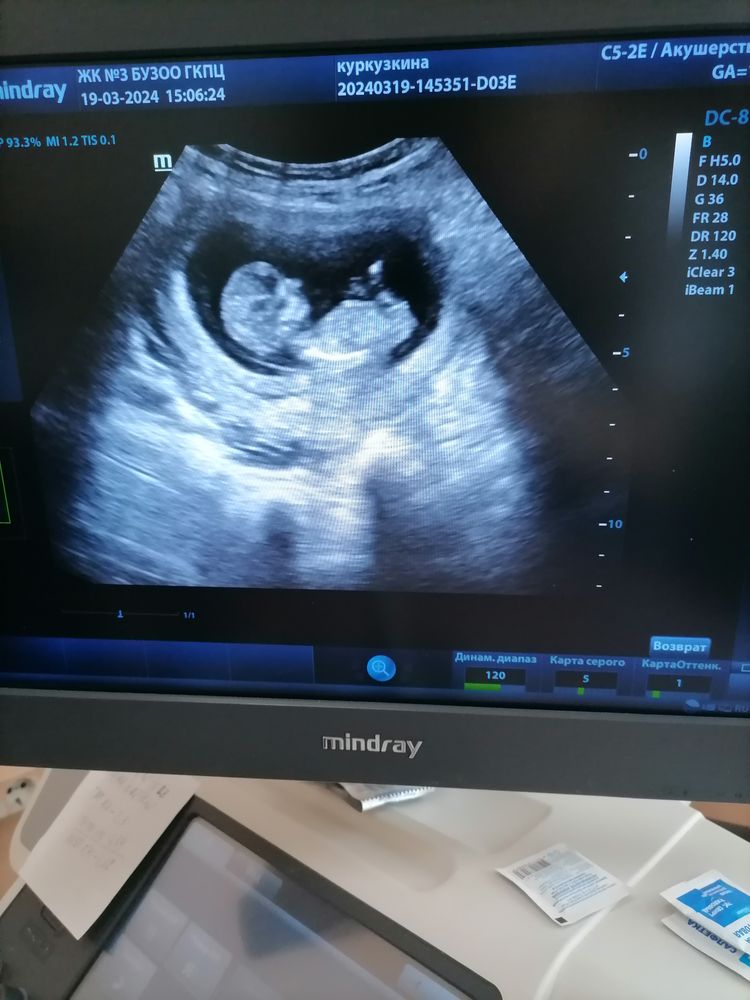

Девочки, кто разбирается. Посмотрите пожалуйста, кто предположительно по бугорку. Изображение

Девочка вроде. Но поближе бы ляльку, мне издалека тяжело смотреть